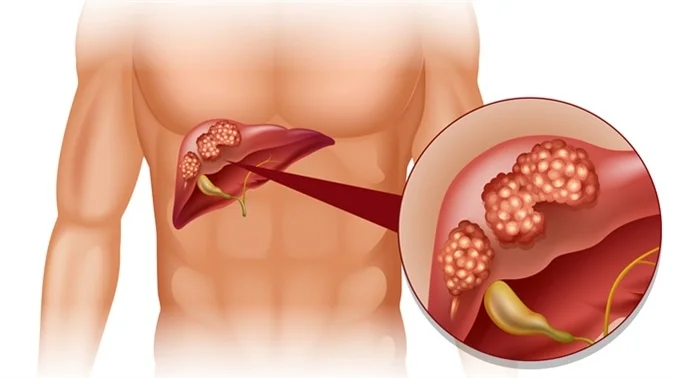

Treatment options depend on the type, location and stage of the cancer. Options may include surgery, chemotherapy, radiation therapy or a combination of these. In general, the earlier a cancer is detected, the better the prognosis.

Localised treatments for liver cancer are administered directly to the cancer cells or the area surrounding the cancer cells. Some treatments use image-guided techniques (interventional radiology). Localised treatments may be recommended for people who can’t undergo surgery:

- Radiofrequency ablation – uses an electric current to heat and destroy cancer cells. Thin needles are inserted into small incisions in the abdomen, using an imaging test as a guide.

- Cryoablation – uses extreme cold to destroy cancer cells. An instrument (cryoprobe) containing liquid nitrogen is placed directly onto the liver tumours, guided by ultrasound images.

- Alcohol injection – pure alcohol is injected directly into tumours causing the tumour cells to die.

- Chemoembolization – chemotherapy (anti-cancer) drugs are injected directly to the liver.

- Radioembolization – tiny glass spheres containing radiation are injected directly into the liver.